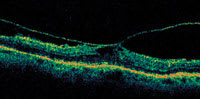

Figure 1: Optical coherence tomography image showing vitreomacular traction syndrome. |

In patients with more advanced cataract, ophthalmoscopy as well as fundus photography and fluorescein angiography may be hindered to variable degrees. Optical coherence tomography (OCT) may give surprisingly good images through relatively small pupils and moderately dense lens opacities (Figure 1). OCT is invaluable in patients with an abnormal-appearing macula who are considering cataract surgery. Other testing (such as fluorescein or indocyanine green angiography) may be used, but are not generally used as a screening tool.